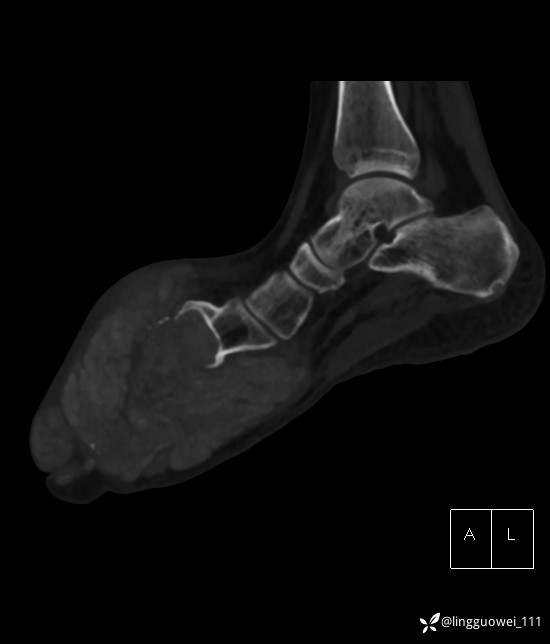

28岁男性,工作中遇到的足部最大的肿块,已补充临床资料。

28岁男性,足部肿块逐渐增大2年。能找到病因吗?

患者于2年余前高嘌呤饮食及大量饮酒后出现全身多处关节痛风石,以右足第一跖趾关节和右手为显,局部红肿热痛反复发作,自行口服药物后可缓解(药物可疑为强的松、双氯芬酸钠等,具体不详)。2年来右足痛风石明显增大,约10cm*5cm*15cm,局部红肿发热,3天前患者再次大量饮酒后痛风石顶部破溃,可见4cm*3cm皮损,较多白色豆渣样分泌物流出,为求进一步治疗来诊,门诊诊断为“右足痛风石破溃伴感染”, 收住院拟手术治疗,患者起病以来,无发热,精神佳、胃纳好、睡眠佳,大小便正常。

专科检查:右足外观畸形,足背部可见巨大痛风石形成,痛风石大小约10cm*5cm*15cm,局部皮肤红肿发热,痛风石顶部破溃,可见4cm*3cm皮损及白色豆渣样分泌物流出;痛风石界限清,质偏硬,局部触及波动感,无压痛,移动度差。右足踇趾及第2趾被痛风石压迫,关节活动受限。肢端血运、感觉无异常。 右手稍肿胀,2-5指背侧可见多发痛风石形成,最大者约花生米大小,皮肤完整未破溃,痛风石界限清,质偏硬,局部触及波动感,无压痛,移动度差。